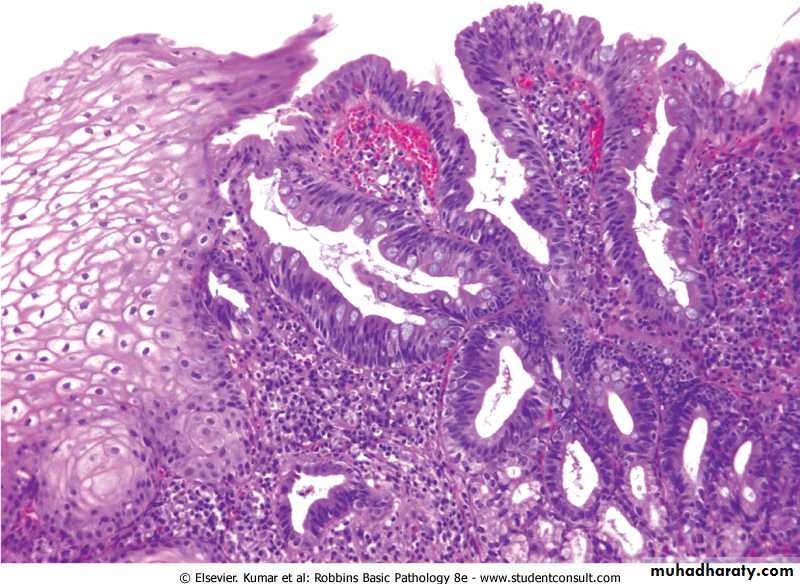

Barrett esophagusReplacement of squamous epithelium by columnar epithelium with goblet cells

Complication of long-standing reflux esophagitisDanger: risk of adenocarcinoma

screen for high-grade dysplasia

Barrett Esophagus